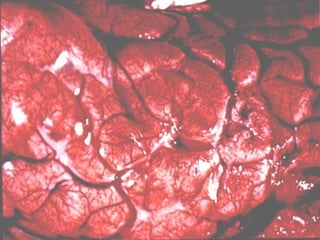

MENINGITIS BACTERIANA Anatomía Patológica Hallazgos macroscópicos: Exudado purulento en la base o convexidad del cráneo. Natas de Fibrina. Daño a pares craneales. Obstrucción del drenaje del L.C.R.

MENINGITIS BACTERIANA Anatomía Patológica Hallazgos macroscópicos: Necrosis del tejido cerebral. Vasculitis. Hemorragia y trombosis de los senos venosos. Abscesos.

MENINGITISBACTERIANA Anatomía Patológica Hallazgos macroscópicos: Exudado purulento en la base o convexidad del cráneo. Natas de Fibrina. Daño a pares craneales. Obstrucción del drenaje del L.C.R.

MENINGITIS BACTERIANA AnatomíaPatológica Hallazgos macroscópicos: Necrosis del tejido cerebral. Vasculitis. Hemorragia y trombosis de los senos venosos. Abscesos.